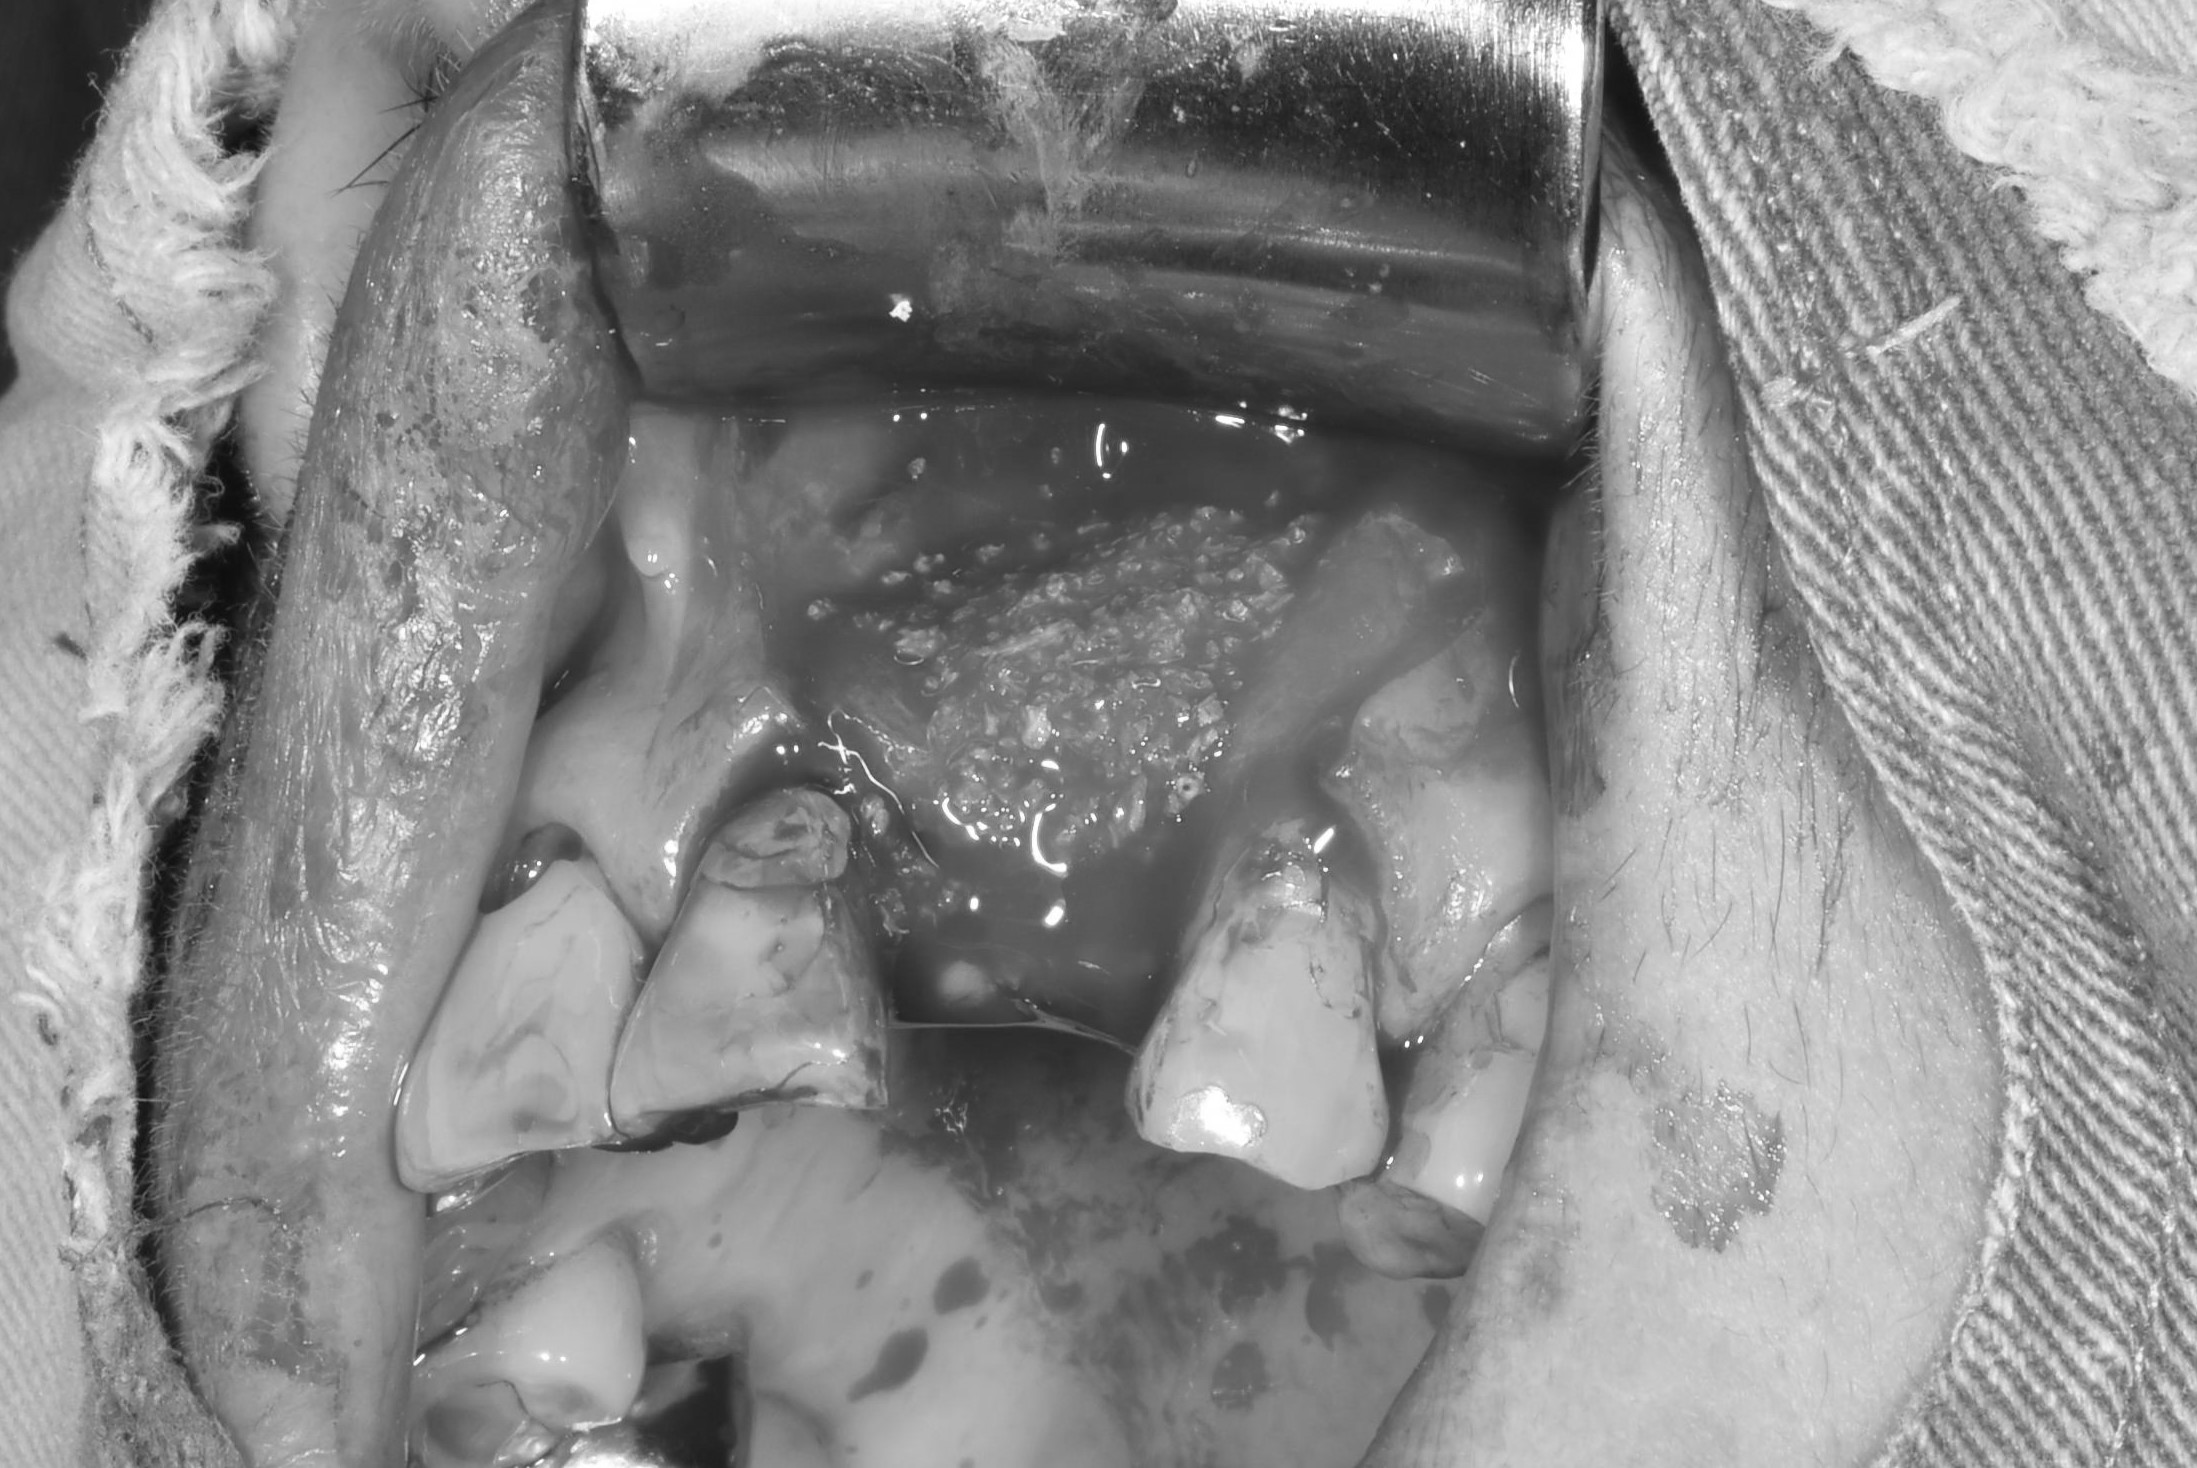

案例二

骨頭明顯凹陷

翻瓣補骨的區域

補入所需的骨粉

完成後依骨頭恢復裝況,需定期回診給醫生評估是否進行下一個階段